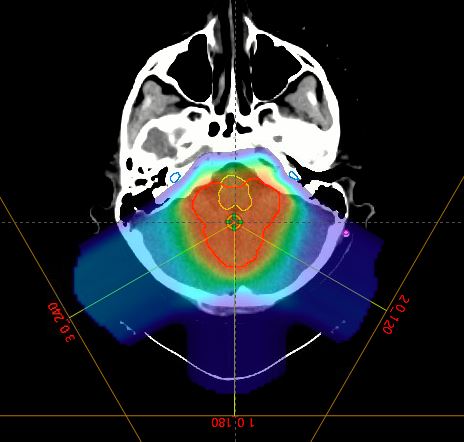

Feltteknikken består af 3 coplanare felter

Et direkte bagfra og to der er vinklede så dosis til cochlea minimeres. Primær plan: Vær omhyggelig med dosis til BrainStem og spinalCord C1 (evt. c2, c3 c4 hvis der er CTV så kaudalt) helst under ordineret dosis, der hvor boost CTV er tæt på OAR Boost dosis varierer alt efter malignitet og dosis på primær planen